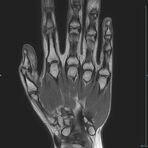

Gelenke

Hand

• Beurteilung von Knochen, Bändern und anderen Weichteilstrukturen der Gelenke nach Unfall.

• Arthrosediagnostik (Knorpelschaden)

• Ausbreitungsdiagnostik bei Gelenkentzündung, z.B. im Rahmen von rheumatischen Grunderkrankungen